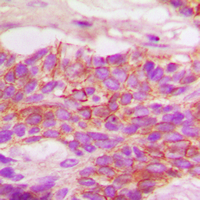

IHC (Immunohiostchemistry)

(Dilution: WB: (1/500 - 1/1000), IH (1/100 - 1/200), IF/IC (1/100 - 1/500), IP (1/10 - 1/100)Immunohistochemical analysis of HER2 (pY1248) staining in human breast cancer formalin fixed paraffin embedded tissue section. The section was pre-treated using heat mediated antigen retrieval with sodium citrate buffer (pH 6.0). The section was then incubated with the antibody at room temperature and detected using an HRP conjugated compact polymer system. DAB was used as the chromogen. The section was then counterstained with haematoxylin and mounted with DPX.)